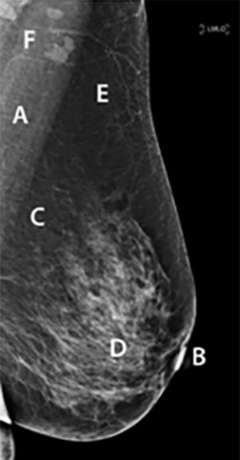

The breasts extend from the second to sixth rib and are anchored to the pectoralis major fascia via the Cooper ligaments1. As the breasts mature and sag due to the stretching of the Cooper ligaments, they can further extend below the sixth rib. Horizontally, the breast extends from the side of the sternum to the midaxillary line, where the tail segment of breast tissue called the axillary tail of Spence resides2. The nipple is commonly located in the center of the breast, superior to the inframammary crease (the inferior fold made by the breast tissue), lateral to the midclavicular line, and at the level of the fourth rib1. The areola is a hyperpigmented, ovular area of skin that concentrically surrounds the nipple3. The nipple and areola together are referred to as the nipple areola complex (NAC), an anatomical classification important in surgical procedures such as mastectomies4. Posterior to the areola is the retro-areolar region, which appears as a triangular-shaped zone in mammograms and can potentially hide breast tumors5. The breast contains the mammary gland, which produces milk that is secreted through outlets in the nipple. The mammary gland is made up of glandular, adipose, and fibrous tissue.

Adipose and dense fibrous tissue are interspersed between the lobes and around the breast1,3. The stroma in which these tissues occupy are divided into three regions: the subcutaneous part between the skin and gland, the intraparenchymal portion lying between the lobes and lobules, and the retromammary portion which is located behind the gland3. Cooper’s ligaments arise from the superficial layer of the subcutaneous superficial fascia and are suspensory ligaments that provide structural support to the parenchyma3. On mammographic imaging, the adipose tissue is radiolucent while the stroma appears radiopaque3.

As mentioned previously, the breast mainly sits anterior to the pectoralis major fascia and muscle. In mammograms, the pectoralis major muscle can be seen as a slightly radiopaque, linear structure located posterior to the breast tissue3. The sternalis muscle is a bandlike structure that runs longitudinally along the medial border of the sternum, bulging anteriorly as the patient is placed in the decubitus position and relaxes the muscle10. The sternalis muscle can be most clearly seen in the craniocaudal projection in mammograms as an irregular opaque body located medially to the breast10. Laterally, the external oblique muscle runs along the inferolateral edge of the breast while the rectus abdominis establishes the inferior border of the breast. Moreover, the serratus anterior runs along the lateral aspect of the chest wall and breast1.